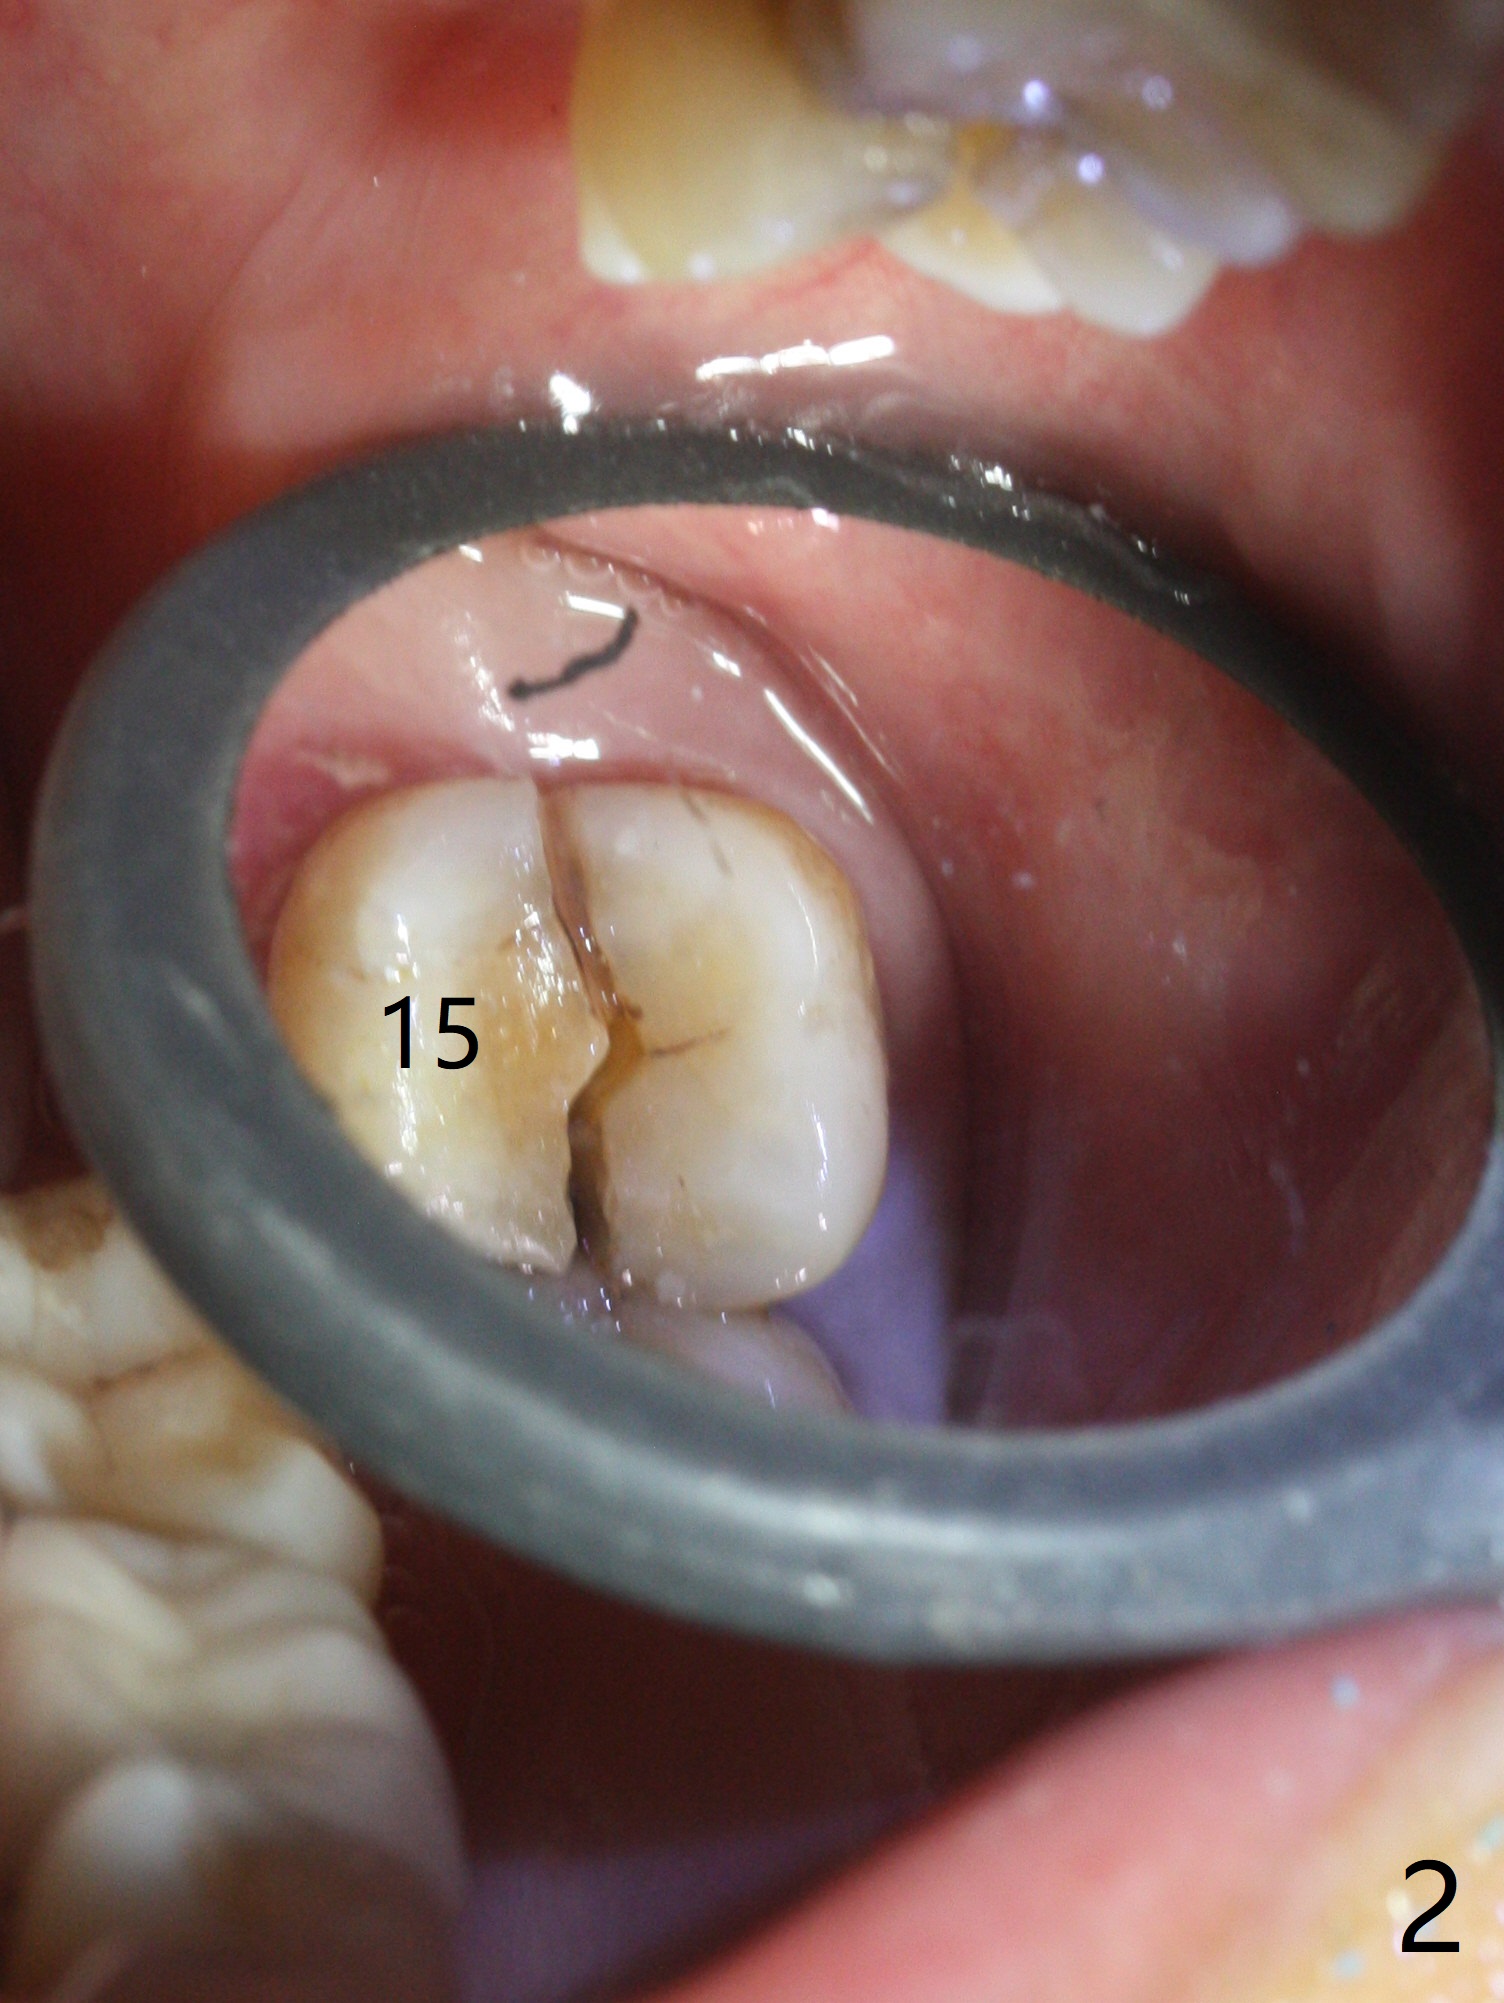

While the tooth #2 has a mesiodistal crack line with symptom (Fig.1 arrowheads, crown pending), the tooth #15 has a mesiodistal fracture (Fig.2). Immediately preop 5x5 cm CBCT (Fig.3) confirms the palatal (P) fracture with palatal bone loss. Although a 5x7.3 mm implant fits the site by design (Fig.4), a much longer implant is required to achieve primary stability past the sinus floor using IBS Magic Expanders (Fig.5,6 (20-30 Ncm; sinus lift with PRF membrane and allograft)). In contrast, primary stability could not be obtained by engaging dummy implant to the socket walls. A short implant without sinus lift is associated with less obvious complication such as fibrointegration. The implant seems osteointegrated 4.5 months postop (Fig.7). The abutment is changed to 6.5x4(5) mm before impression. There is no bone loss 5 months post cementation (Fig.8 (11 months postop)). It is the same 2.5 years post cementation (Fig.9,10).